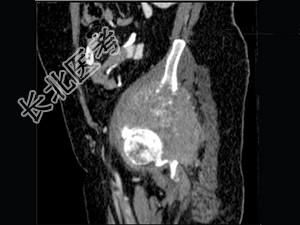

- 单项选择题男,56岁, 肺癌术后2年余,左髋部疼痛, 夜间加重,结合图像, 最可能的诊断是 ( )

B、骨转移